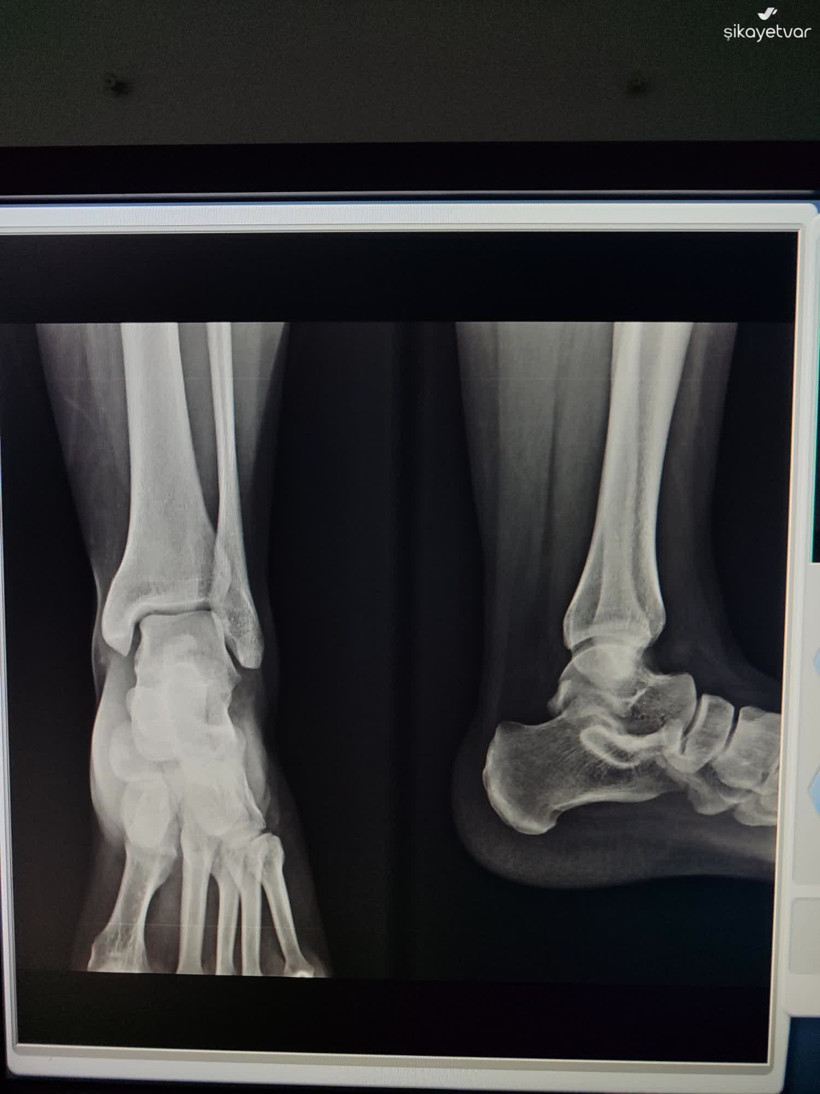

Kocaeli’de bir vatandaşın Şikayet Var adlı internet sitesinde yaptığı paylaşım, “Acil serviste kim acil?” sorusunu yeniden gündeme taşıdı. Körfez Devlet Hastanesi Acil Servisi’nde yaşandığı iddia edilen olay, sosyal medyada ve kamuoyunda tartışma yarattı. Şikayet Var platformunda yer alan paylaşıma göre olay, 13 Aralık 2025 Cumartesi gecesi saat 22.30 sıralarında Kocaeli Körfez Devlet Hastanesi Acil Servisi Triaj bölümünde yaşandı. Vatandaş, eşinin ayağında ya da ayak bileğinde çatlak olabileceği şüphesiyle hastaneye başvurduklarını ve acil olarak röntgen çekilmesi gerektiğini belirttiğini ifade etti.

13.12.2025 tarihinde saat 22.30 sularında, eşimde kırık ya da çatlak olabileceği şüphesiyle Kocaeli Körfez Devlet Hastanesi Acil Servis Triaj Bölümüne başvurdum. Acil olarak röntgen çekilmesi gerektiğini belirtmeme rağmen, triajda bulunan bir erkek ve bir kadın personelin ilgisiz ve laubali tavırlarıyla karşılaştım. Durumu defalarca anlatmama rağmen, yalnızca yeşil alana yönlendirilmekle yetindiler ve sürece dair hiçbir şekilde yardımcı olmadılar.